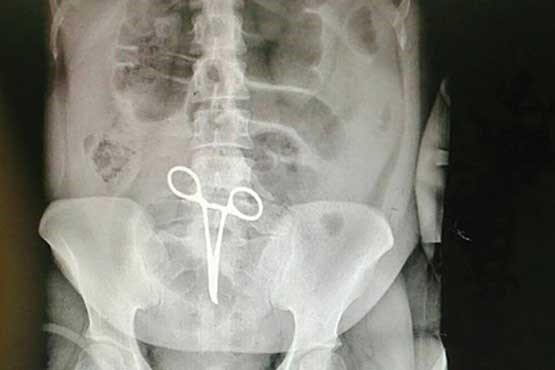

جا ماندن پنس جراحی در "شکم" بیمار! +عکس

جا ماندن پنس جراحی در شکم بیمار 35 ساله او را دوباره راهی اتاق عمل کرد.

به گزارش شهدای ایران به نقل از صدا و سیما، این بیمار به علت درد شکم به بیمارستان شهید رجایی قزوین مراجعه کرد که پس از معاینات پزشکی مشخص شد در شکمش پنس جراحی جا مانده است.

ریحانه چگینی، مسئول اتاق عمل مرکز آموزشی - درمانی شهید رجایی قزوین در این باره گفت: در عمل جراحی سه ساعته، پَنس از شکم بیمار خارج شد. این پنس حدود دو ماه قبل در عمل جراحی بیمار در یکی از بیمارستانهای شهریار استان البرز در شکمش جا مانده بود. حال عمومی بیمار رضایتبخش است.